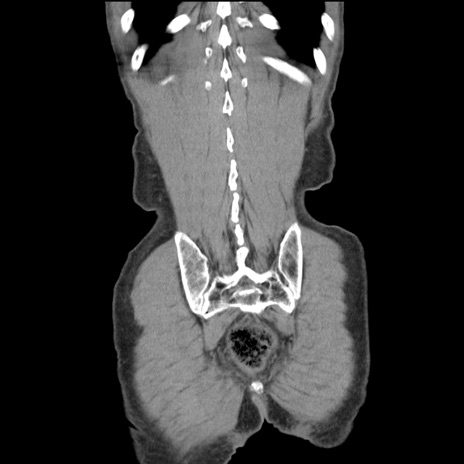

症例11(冠状断像)

【症例】 60歳代男性

【主訴】 下腹部痛

【現病歴】 本日夜中より下腹部痛の症状認め、受診。

【既往歴】 膀胱癌(膀胱全摘+尿管皮膚瘻術) 、胃癌術後

【身体所見】 BT 35.3℃、PR 58/min、BP 136/98mHg、腹部平坦、軟、腸蠕動音±、ストマ留置あり、左上腹部~正中部に圧痛あり、反跳痛なし。

【データ】WBC 5100、CRP0.01